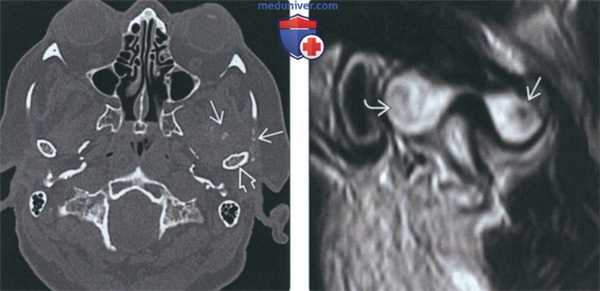

(Слева) На аксиальной КТ правого ВНЧС в коаном окне спереди ог мыщелка визуализируются «грубые» обызвеавления. Кортикальная пластинка мыщелка интактна, наружный полюс склерозирован вследавие дегенеративных изменений.

(Справа) На панорамном изображении правого ВНЧС визуализируется мыщелок обычных размеров и формы. Спереди и сзади от мыщелка определяется неоднородное затемнение. Объемное образование имеет большие размеры и приводит к рааяжению суаавной капсулы.

(Слева) На аксиальной КТ у этого же пациента вдоль внутреннего, наружного, переднего края мыщелка визуализируются множественные обызвествленные/оссифицированные свободные тела различного размера. Су аавная капсула в значительной степени растянута.

(Справа) На косом корональном срезе (Т1) у этого же пациента в пределах растянутой капсулы визуализируются обызвествленные/оссифицированные свободные тела.

(Слева) На аксиальной КТ в костном окне у пациента с синовиальным хондроматозом левого ВНЧС спереди и снаружи от мыщелка определяется объемное образование с множественными точечными обызвествлениями.

(Справа) На косой сагиттальной MPT(Т2 ВИ) определяется неоднородный сигнал позади мыщелка, сопоставимый с хрящевыми узлами, и обызвествление/оссификация спереди от него.